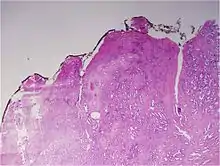

![]() Gleason grade — Lower grades are associated with small, closely packed glands. Cells spread out and lose glandular architecture as grade increases. Gleason score is calculated from grade as described in the text. |

The Gleason grading system is used to help evaluate the prognosis of men with prostate cancer using samples from a prostate biopsy. Together with other parameters, it is incorporated into a strategy of prostate cancer staging which predicts prognosis and helps guide therapy. A Gleason score is given to prostate cancer based upon its microscopic appearance.[1] Cancers with a higher Gleason score are more aggressive and have a worse prognosis. Pathological scores range from 2 to 10, with higher numbers indicating greater risks and higher mortality. The system is widely accepted and used for clinical decision making even as it is recognised that certain biomarkers, like ACP1 expression, might yield higher predictive value for future disease course.[2]

The Gleason grade is based on tissue architectural patterns rather than purely cytological changes. These tissue patterns are classified into 5 grades, numbered 1 though 5. Lower numbers indicate more differentiation, with pattern 5 being the least differentiated.[4][7] Differentiation is the degree to which the tissue, in this case the tumor, resembles native tissue. Greater resemblance (lower grade) is typically associated with a better prognosis.